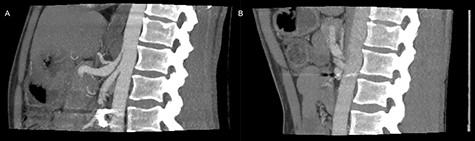

The patient was discharged on the third postoperative day, but readmitted 4 days postoperatively due to a minor abdominal wound dehiscence, which was sutured under general anesthesia. On follow-up computed tomography the arterial stenosis was repealed and the pseudoaneurism collapsed (Fig. 3).

Postoperative inspiratory (A) and expiratory (B) computed tomography scan with repealed hook formation as well as stenosis of the celiac artery.